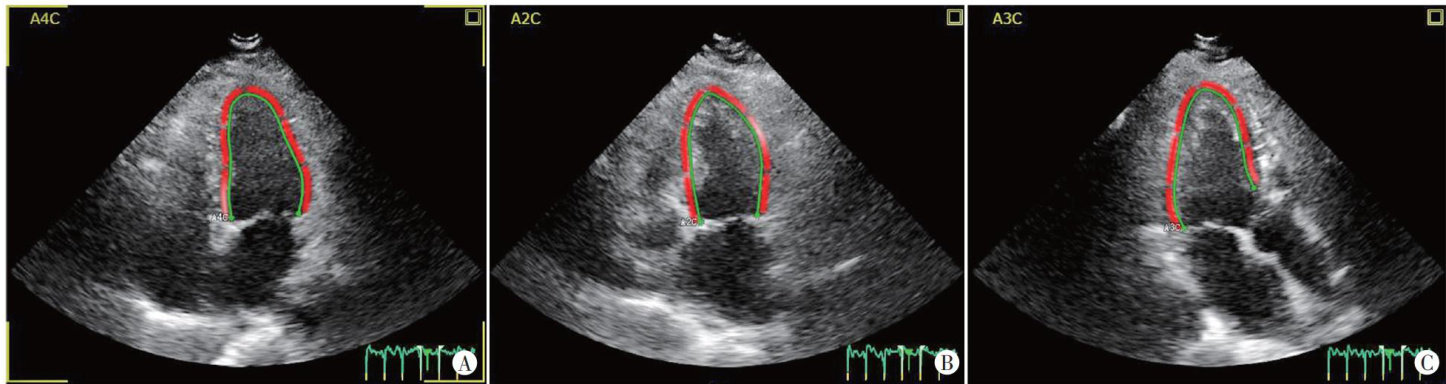

ABSTRACTObjectiveToevaluatealterations inleft ventricular myocardiallongitudinal function in patients with mildtomoderatecoronaryarterystenosis bytwo-(剩余12326字)

二维斑点追踪技术评估冠状动脉轻中度窄患者左室心肌纵向功能的变化